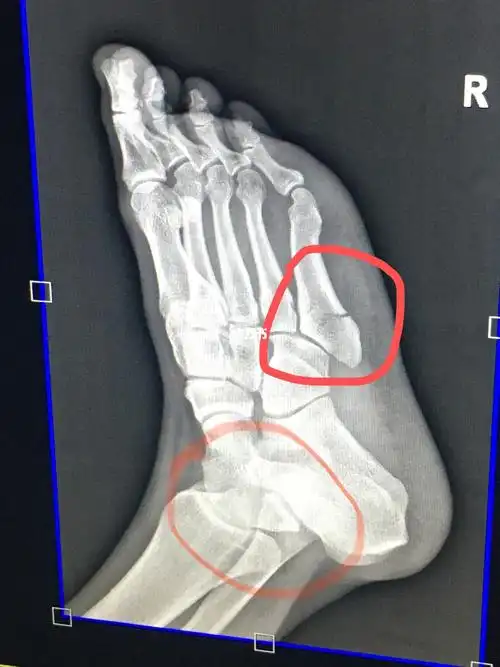

9月26日,踢球落地崴脚,第二天拍片发现第五跖骨骨折,打石膏38天了